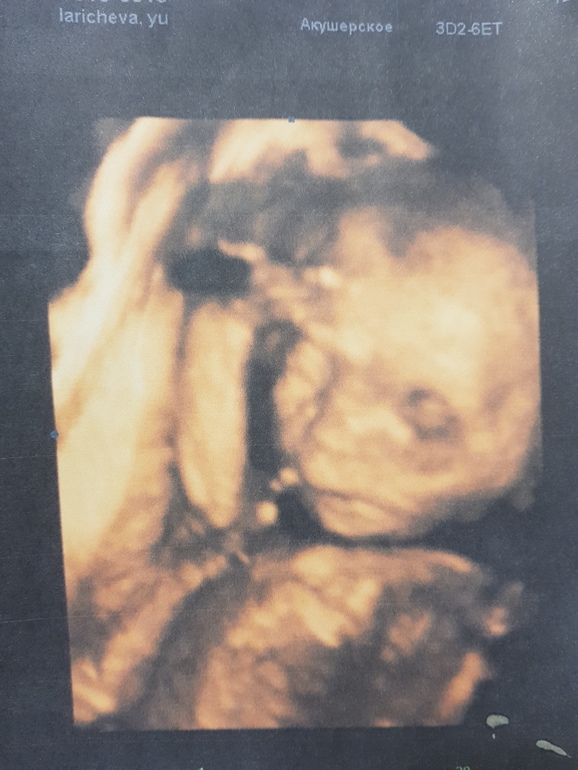

Наш малыш активно шевелиться,Не соскучишься.Еще на меня грусть тоска напала((Сегодня еще на сроке 20.4 были на узи и ходили к Ги.Так классно снова видеть Своего сыночка😍😍😍

Он у нас уже 323 гр Чистой любви)) Лежит головой в низ,Но еще конечно будет вертеться))Вот насторожили меня только кисты в голов.Мозге,Но узист и моя Ги сказали не переживать,Что явление частое(Особенно учитываю что я только переболела Орви)И через пару недель пройдет.Но как тут не переживать?Может у кого было на этом сроке на столько ли частое?Пдр поставили на 4 апреля,на др нашей первой дочери.А как ваше самочувствие односрочницы?